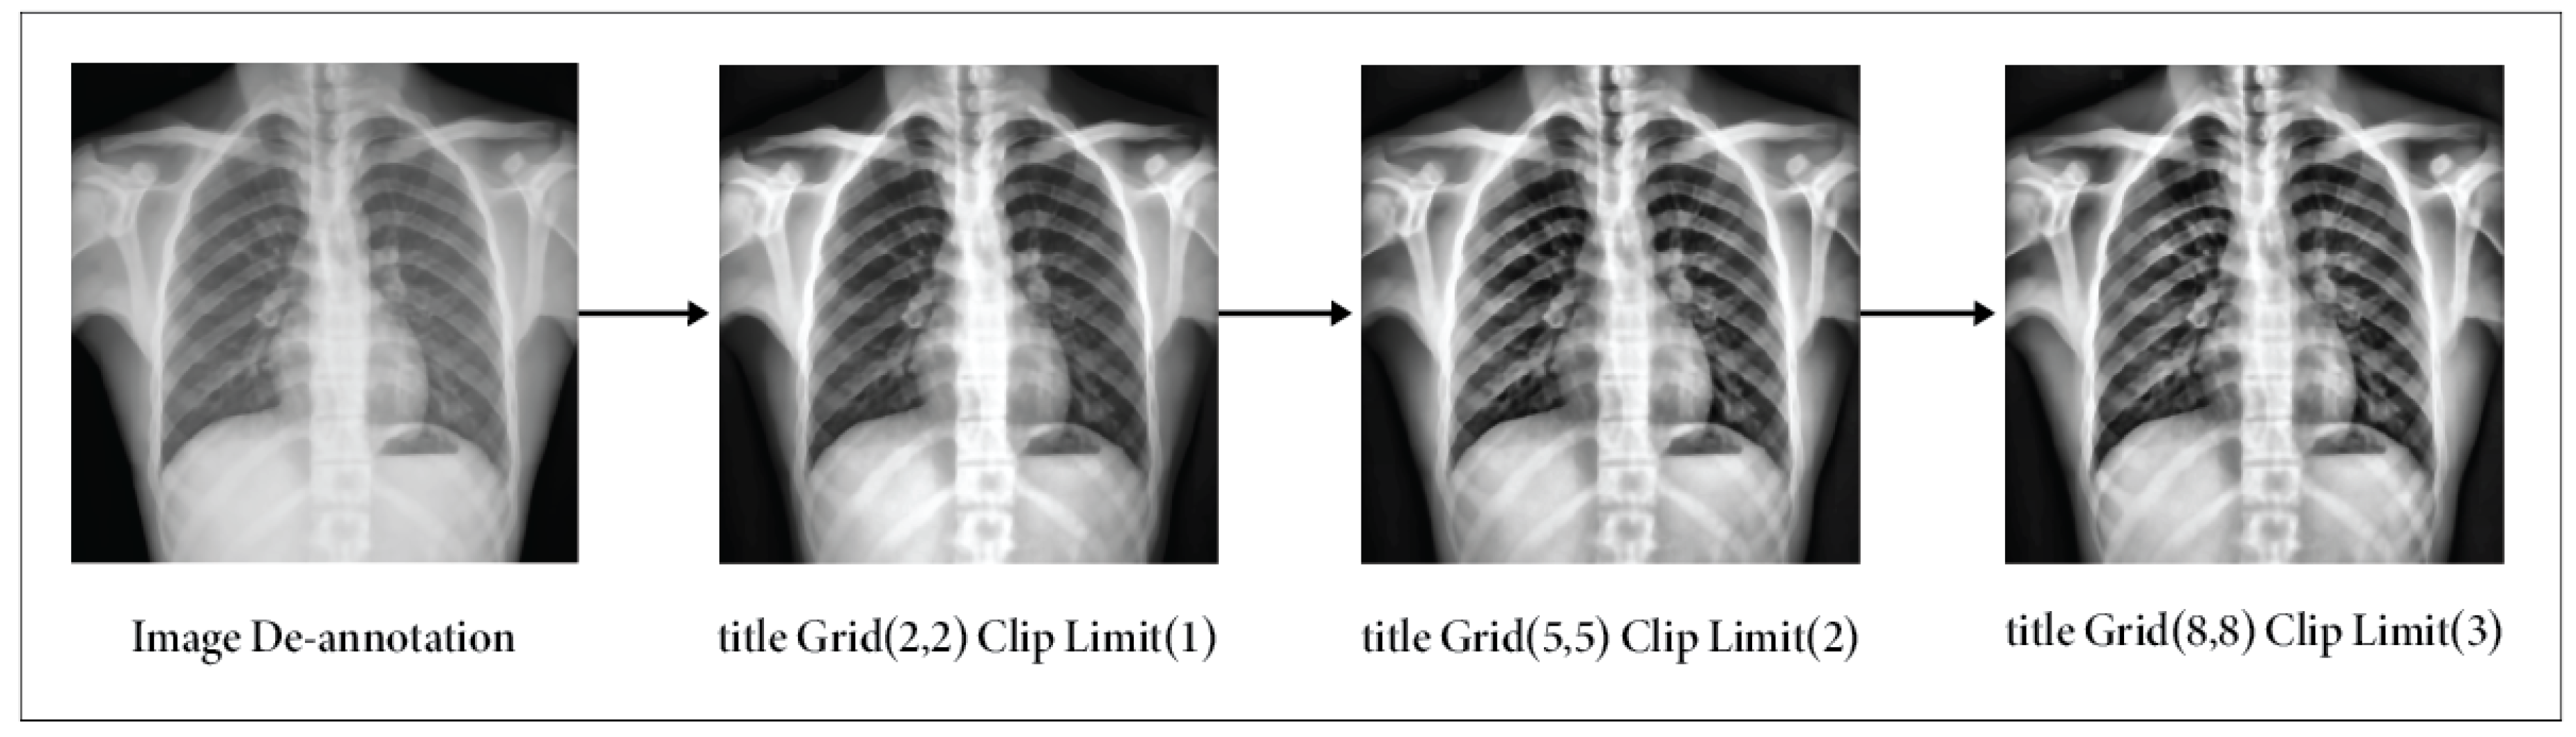

3.2.4. Image Enhancement

- Initially, the RGB image was transformed into an LAB image.

- Subsequently, the CLAHE approach was employed to enhance the L channel.

- Next, the enhanced L channel should be paired with the A and B channels to obtain an enhanced LAB image.

- Eventually, the improved LAB image was converted to revert to its original form as the enhanced RGB image.